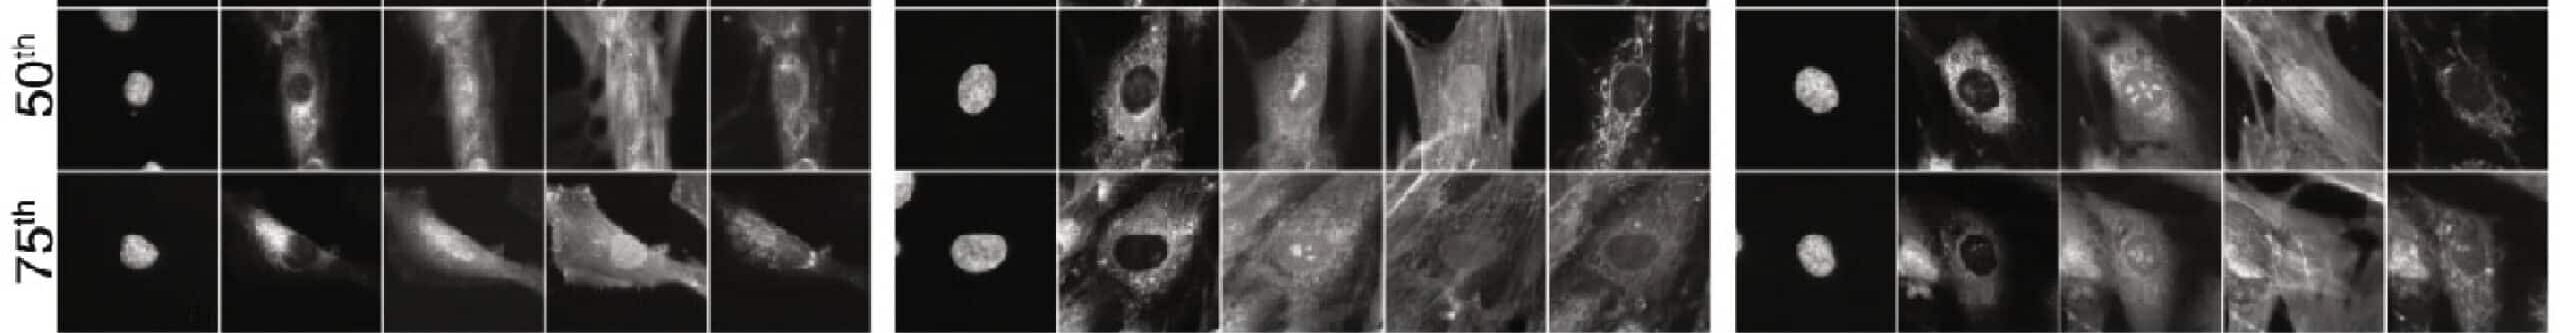

We published a landmark study in Nature Communications demonstrating proof of concept, remarkably, using primary human fibroblasts from a large cohort of Parkinson’s disease patients.

Read the paper: Integrating deep learning and unbiased automated high-content screening to identify complex disease signatures in human fibroblasts

NYSCF has since harnessed this platform, which combines our advantages in scale achieved through automation with cell painting and AI-powered image analysis, to extend these findings in other therapeutic areas and in iPSC-derived cell types. We have further screened libraries, demonstrated the ability to shift disease phenotypes, and are layering in additional readouts.